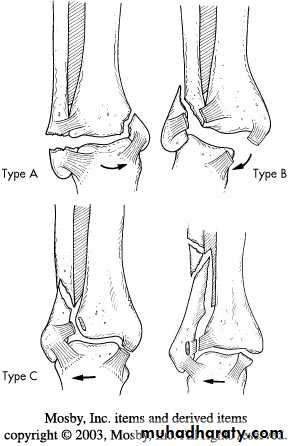

Danis-Weber classification (based on the level of fibular fracture)

Type A: a fibular fracture below syndesmosis and oblique fracture medial maleolus.

Type B: fibular fracture at syndesmosis + disruption of ant. Fibers of tibiofibular lig. + fracture of medial malleolus or rupture of deltiod lig.

Type C: fibular fracture above syndesmosis+ tibiofibular lig. (syndesmosis) is torn. Unstable fracture-subluxation of ankle mortise.

DANIS WEBER CLASSIFICATION OF ANKLE FRACTURES